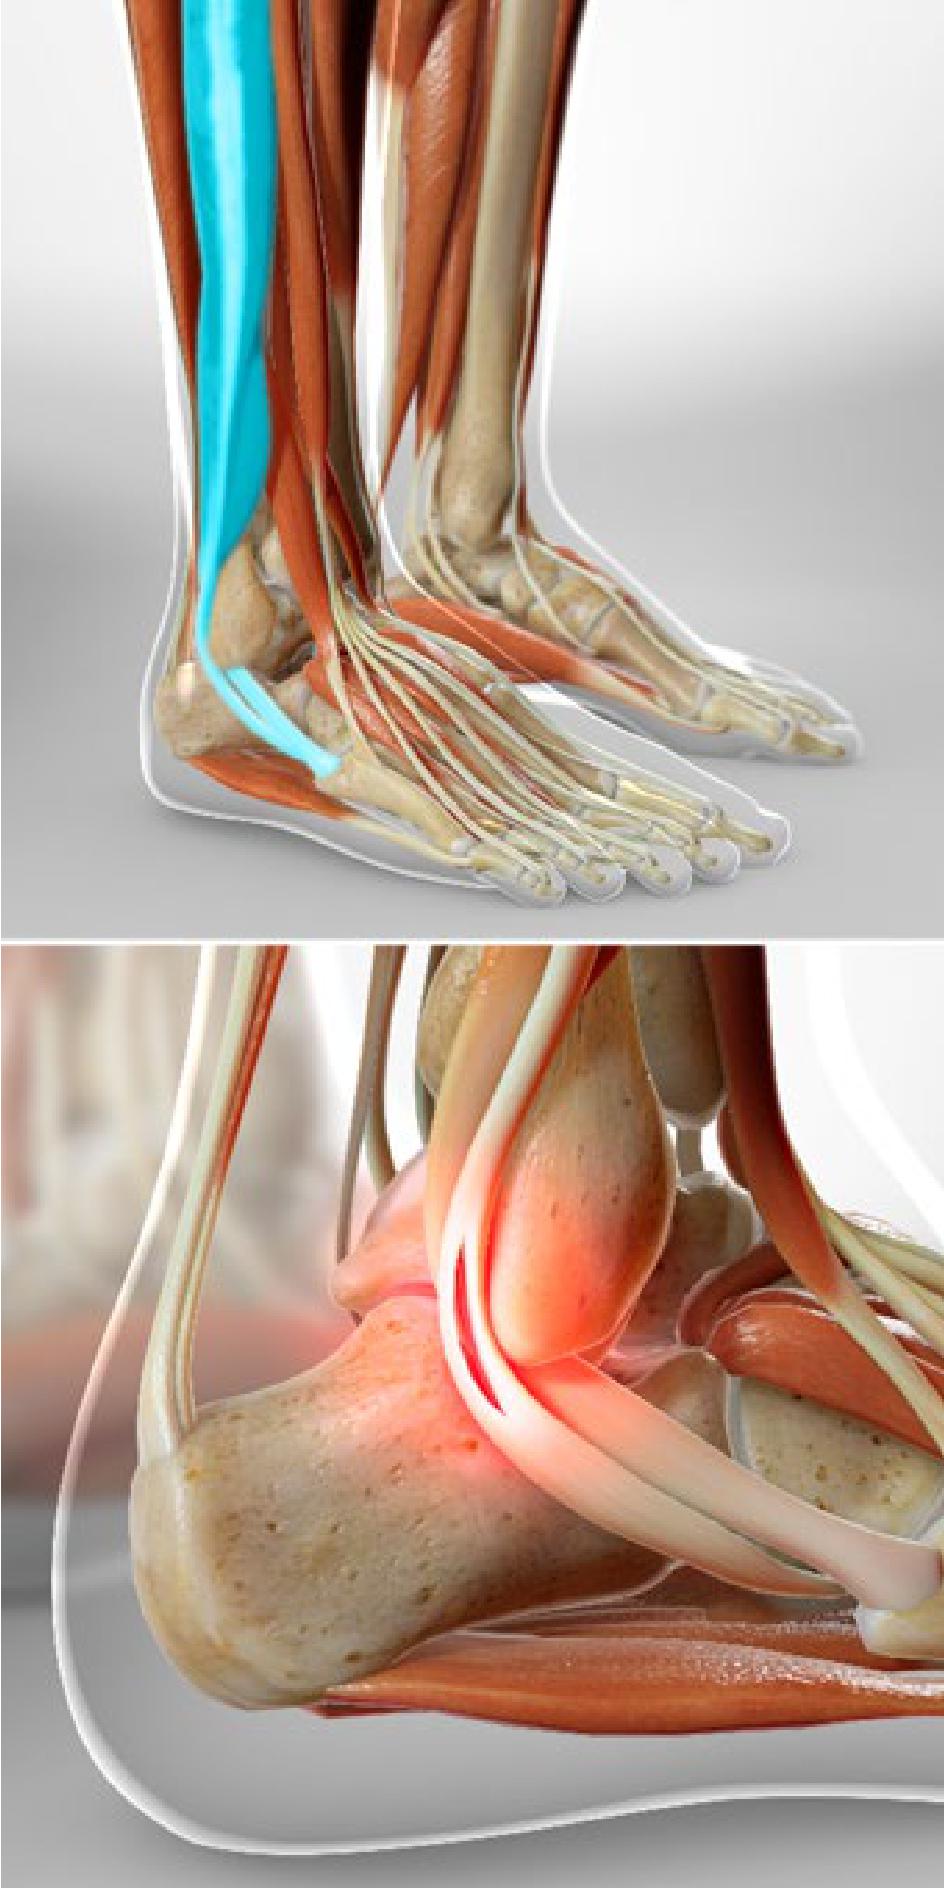

Ankle Ligament Repair- The Ultimate Option To Cure Severe Ankle Problems

dranujchawla.comtendon ligament incisions severe reconstruction sutures screws

dranujchawla.comtendon ligament incisions severe reconstruction sutures screws

intermountainhealthcare.orgAnkle Arthroscopy And Ankle Ligament Reconstruction | Murdoch

intermountainhealthcare.orgAnkle Arthroscopy And Ankle Ligament Reconstruction | Murdoch

murdochorthopaedic.com.auankle surgery arthroscopy arthritis ligament reconstruction foot operation joint procedure time treatment pain do surgical recovery does after bone arthroscope

murdochorthopaedic.com.auankle surgery arthroscopy arthritis ligament reconstruction foot operation joint procedure time treatment pain do surgical recovery does after bone arthroscope